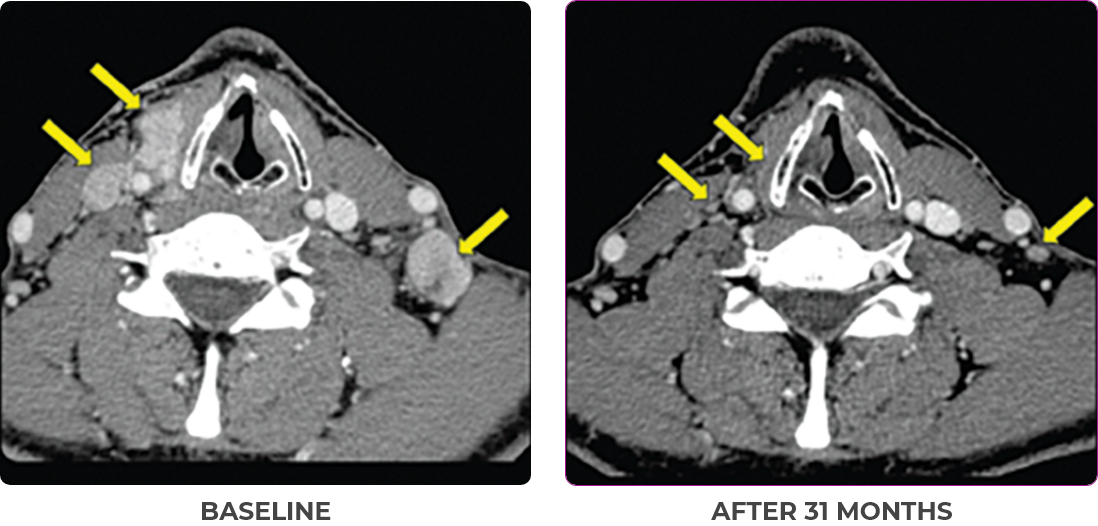

BASELINE

AFTER 31 MONTHS

33-YEAR-OLD MALE4

PATIENT CASE:

METASTATIC, RAIa-REFRACTORY,

PAPILLARY THYROID CANCER1,2

- 33-year-old male

- Progression on RAI and first line systemic therapy

- PRa after 2 cycles of VITRAKVI® (larotrectinib)

- Confirmed partial response on VITRAKVI lasting 55 cycles

Clinical presentation1

- Initially diagnosed at age 27

- Bulky disease in neck and thoracic involvement; metastatic, RAI-refractory papillary thyroid cancer

VITRAKVI treatment1

- VITRAKVI 100 mg twice daily orally

Response to VITRAKVI1,2

- Confirmed partial response (92.6% reduction in target lesions)

- Treatment continued for 55 cycles

- VITRAKVI was well tolerated; patient did not have to discontinue due to AEa

- No treatment interruptions or dose reductions

Response in primary and metastatic lesions1

Images courtesy of Dr Steven Waguespack.